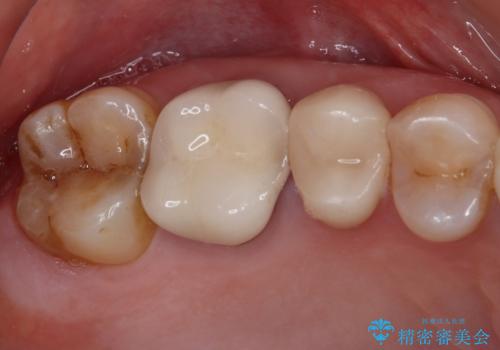

【審美修復】被せ物のみの治療

担当医 河口智英

奥歯の目立つ銀歯をセラミックに オールセラミッククラウン治療